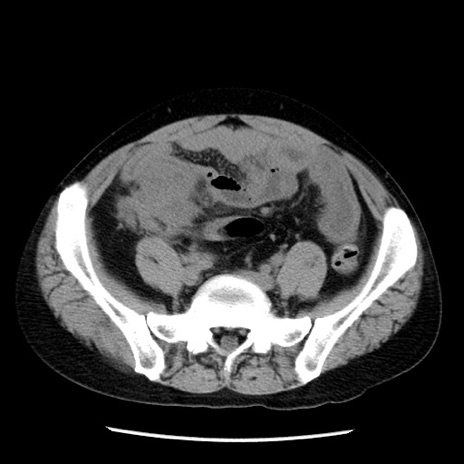

症例29(横断像)

【症例】40歳代男性

【現病歴】2日前から胃痛あり。徐々に周期的な激痛に変化した。本日になっても激痛があるため受診。

【身体所見】意識清明、BT 38-39℃台あり、腹部:膨満、やや硬、右下腹部に圧痛あり。

【データ】WBC 8500、CRP 23.26